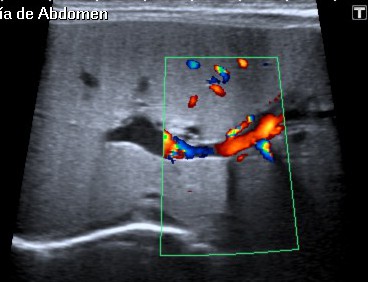

Ecografía:

- Arteria hepática de calibre aumentado.